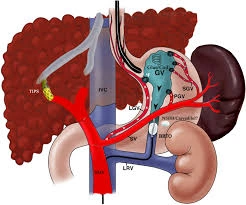

BRTO (Balloon-Occluded Retrograde Transvenous Obliteration)

What is BRTO?

BRTO is a specialized procedure used to treat gastric varices, which are enlarged veins in the stomach caused by portal hypertension.

A catheter with a balloon is inserted into a vein and positioned near the abnormal veins. The balloon temporarily blocks the vein while a special medication is injected to close the varices.

Benefits

Effective control of gastric variceal bleeding

Minimally invasive procedure

Reduced risk of recurrent bleeding

Short recovery time